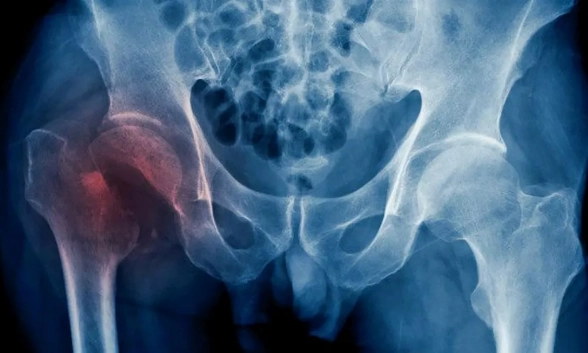

La cadera es una articulación formada por la unión del fémur (hueso del muslo) y el acetábulo (parte de la pelvis). Cuando decimos que un paciente sufre una fractura de cadera, en realidad, hacemos referencia a la extremidad proximal del fémur. Esta lesión es muy frecuente en las personas mayores, ya que tienen los huesos más frágiles por la osteoporosis y mayor riesgo de caídas por problemas de equilibrio o movilidad.

En cuanto a la técnica quirúrgica empleada para tratar la fractura de cadera, existen dos opciones principales: la fijación de la fractura (mediante distintos tipos de osteosíntesis- clavos, placas, tornillos-) y el reemplazo de la articulación por una prótesis. La elección de una u otra depende fundamentalmente, del tipo y la localización de la fractura , aunque cada caso es evaluado detalladamente por el profesional.

“De forma muy generalizada y refiriéndonos al tema en cuestión, podemos decir que la fijación de la fractura se suele realizar aquellas que afectan al macizo trocantérico (extracapsulares), mientras que optamos por una prótesis en aquellas que la zona afectada es el cuello femoral (intracapsulares). "En cualquier caso, el objetivo es lograr una estabilidad óptima que permita al paciente apoyar y caminar lo antes posible, salvo en casos individualizados”, explica el doctor Badillo.